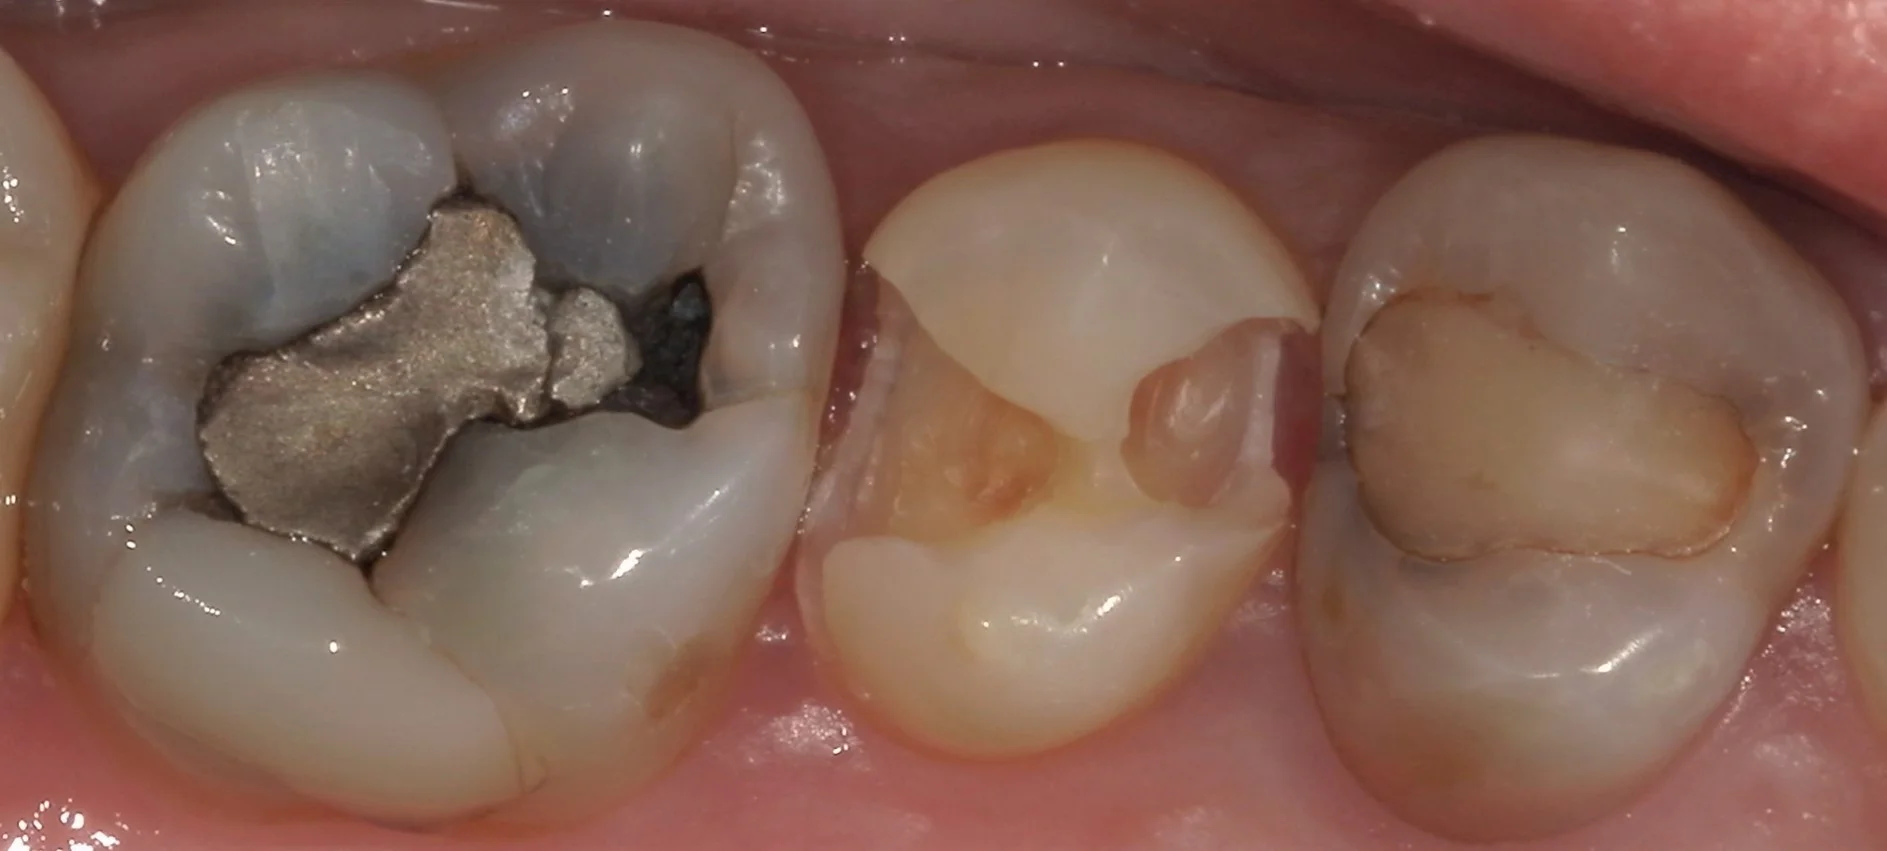

本来の歯の色が出て綺麗になりましたね。

中心部に内面が白く抜けている茶色く丸い楕円があるのが分かると思います。

この白い部分のほんの一層下の部分が神経になります。

今回は神経の露出はなかったので、そのまま詰めていきました。